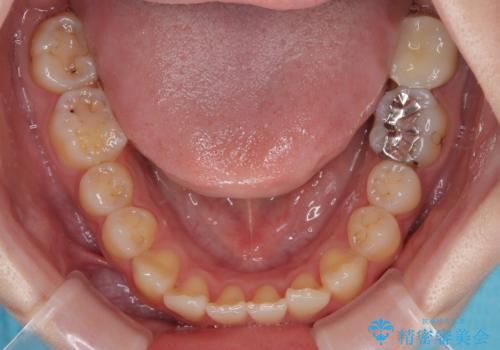

- 過去の歯医者通いの恐怖から虫歯を放置してきたものの、一大決心して来院された患者様です。

神経組織の失活している歯や歯根だけが残っている歯などがあり、全体的に歯石も多く付着している状態でした。

まずは歯石除去とブラッシング方法などの衛生指導を徹底的に行って口腔内環境を改善し、汚れの溜まりやすくなっている親知らずは全て抜去することとしました。

その後、歯根だけとなっている歯はインプラントに、神経組織の失活している歯は根管治療を行い、いずれもオールセラミッククラウンにて補綴治療を行うこととしました。

口腔内の環境が大きく改善し、現在はご自身のプラークコントロールにより良い状態が維持できるようになりました。